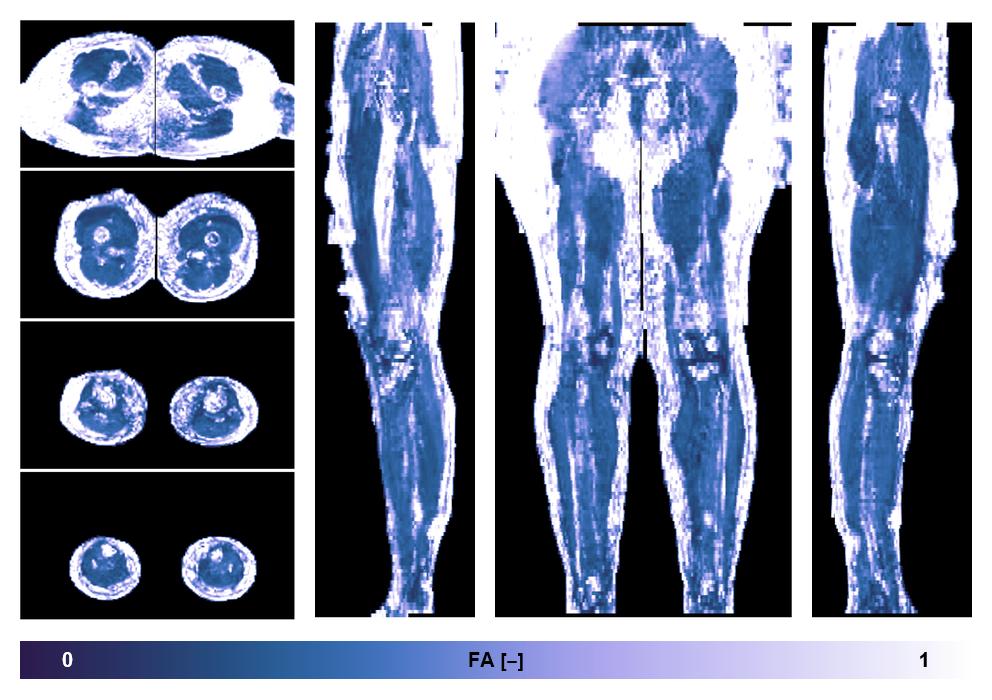

• Fractional anisotropy

IVIM corrected whole leg muscle fractional anisotropy obtained from diffusion tensor imaging.

• SNR of the unweighted image

SNR distribution of the unweighted diffusion data.